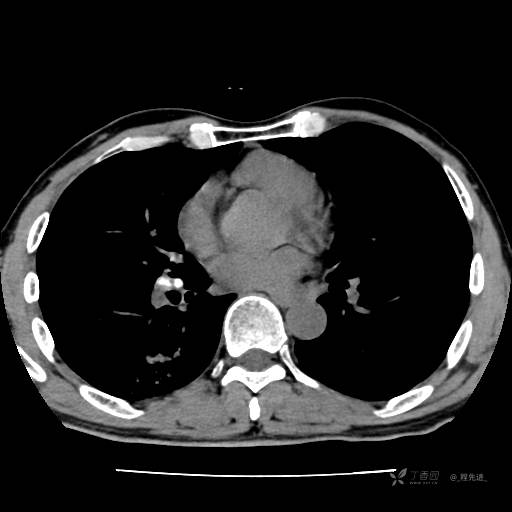

2月特别精彩病例|咳嗽、咳痰20余天,典型病例分享【结果已公布】

患者年龄:51岁

主诉:咳嗽、咳痰20余天

简要病史:20余天前开始出现咳嗽、咳痰症状,阵发性刺激性咳,白色粘痰,不易咳出,无发热,无咯血,无恶心、呕吐等不适,未诊治,咳嗽、咳痰症状持续存在。

体格检查:T:36.3 ℃ P:79 次/分 R:20 次/分 BP:128/64 mmHg,神志清楚,呼吸平稳,双肺呼吸音粗,右下肺闻及细湿性啰音。心率79次/分,节律整齐,各瓣膜听诊区未闻及病理性杂音。腹部未见异常,双下肢无水肿。

辅助检查:我院门诊胸部CT示:如下。心电图:窦性心律;正常心电图。